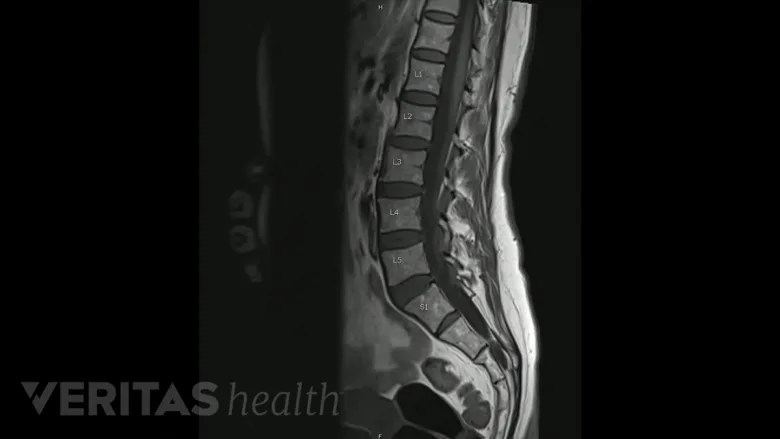

Las resonancias magnéticas muestran detalladamente los tejidos lumbares para diagnosticar la degeneración del disco.

Un diagnóstico definitivo de enfermedad degenerativa del disco lumbar puede requerir una resonancia magnética para asegurarse de que no hay otros problemas que contribuyan al dolor, como una fractura o una hernia discal. Si es necesaria una intervención quirúrgica, se requiere una prueba de imagen antes de la intervención para localizar con precisión el disco degenerado y planificar la cirugía.

Una resonancia magnética utiliza un imán de alta potencia para alinear y detectar moléculas de agua en el cuerpo, lo que permite a los médicos visualizar tejidos blandos como músculos, ligamentos, tendones y discos vertebrales. Las resonancias magnéticas se basan en el magnetismo en lugar de la radiación, que se utiliza en rayos X y tomografías computarizadas, por lo que el riesgo de una resonancia magnética es mínimo y las exploraciones no son dolorosas.

Las resonancias magnéticas pueden proporcionar información útil sobre lo siguiente:

- Altura del disco

- Forma del disco

- Desgaste de la plataforma inferior

- Nervios pinzados

- Hidratación del disco (si hay poca o ninguna hidratación, puede denominarse “disco negro”, ya que el disco se verá negro en la resonancia magnética)

Los estudios demuestran que los hallazgos en la RM de una degeneración discal leve o significativa suelen darse en exámenes de pacientes con distintos grados de dolor, ya sea intenso, mínimo o nulo. Además, muchas afecciones dolorosas pueden no aparecer en una resonancia magnética, como un desgarro en los anillos externos del disco o en algunos casos de discos herniados. Por este motivo, el diagnóstico no puede basarse únicamente en pruebas de imagen, sino que debe combinarse con la historia clínica y el examen físico.